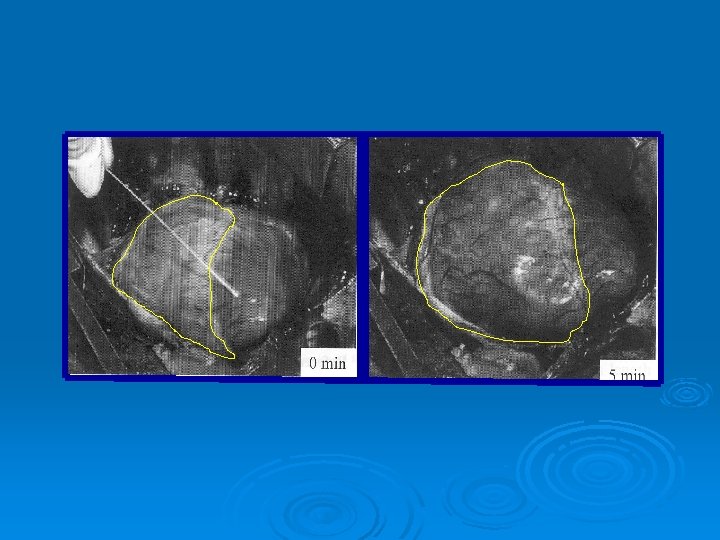

The critical importance of minimal delay between chest compressions and subsequent defibrillation: an haemodynamic explanation Steen S. et al. Resuscitation 2003; 58: 249 -258